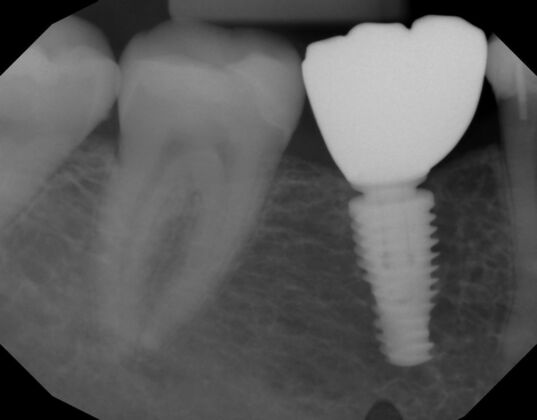

Patient lost lower first molars and required two lower implants with two lower screw retained crowns